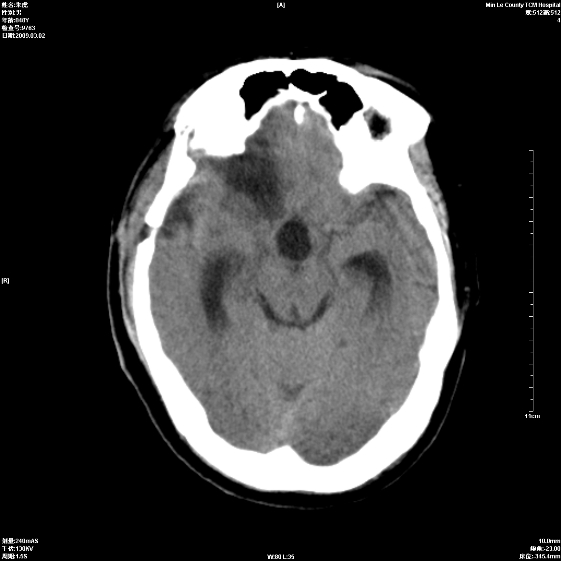

标题: CT18444:男颅咽瘤术后一月复查脑积水增多 [打印本页]

标题: CT18444:男颅咽瘤术后一月复查脑积水增多

右侧额叶局软化灶,梗阻性脑积水。

右额叶软化灶。梗阻性脑积水。

手术后改变

1、右额叶脑软化

2、脑积水

1)右侧额颞部颅骨术后改变。2)右侧额颞叶脑软化灶。3)脑积水(梗阻性)。

手术后改变1、右额叶脑软化2、梗阻性脑积水。